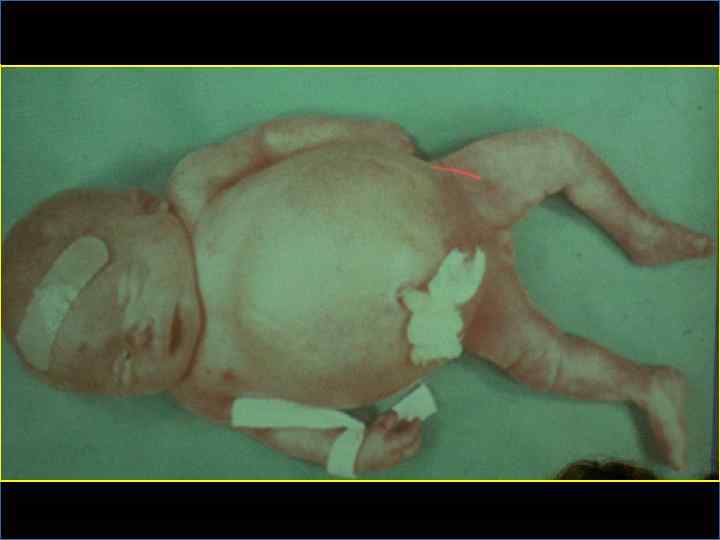

ГЕМОЛИТИЧЕСКАЯ БОЛЕЗНЬ ПЛОДА ТЯЖЕЛОЙ СТЕПЕНИ § Частота 20 -25% § Пренатальное лечение – внутриматочные трансфузии до 26 -32 недель беременности (введение резус-отрицательной крови резусположительному плоду) § Гемоглобин у плода менее 70 г/л (норма 160 -180 г/л) § Водянка плода: генерализованный отек, гепатоспленомегалия, гепатоцеллюлярные нарушения, застойная сердечная недостаточность, экстрамедуллярный эритропоэз, отек плаценты

ГЕМОЛИТИЧЕСКАЯ БОЛЕЗНЬ НОВОРОЖДЕННОГО § Гемолитическая анемия без желтухи и водянки (наиболее легкая форма ) § Гемолитическая анемия с желтухой и водянкой

ГЕМОЛИТИЧЕСКАЯ БОЛЕЗНЬ НОВОРОЖДЕННОГО Клинические признаки Степень тяжести гемолитической болезни легкая средняя тяжелая Анемия (Hb в пуповинной крови) ≥ 150 г/л 149 -100 г/л ≤ 100 г/л Желтуха (билирубин в пуповинной крови) ≤ 85, 5 мкмоль/л 85, 6 -136, 8 мкмоль/л ≥ 136, 9 мкмоль/л Пастозность подкожной клетчатки Пастозность и асцит Универсальный отек Отечный синдром

Лечение гемолитической анемии новорожденного § Гемолитическая анемия без желтухи и водянки – инфузионная терапия, фототерапия (дневной или синий свет, дл. волны-460 -480 нм) § Гемолитическая анемия с желтухой – заменное переливание крови показания – билирубин- более 100 мкмоль/л, почасовой билирубин- более 10 мкм § Гемолитическая анемия с желтухой и водянкой – лечение не проводится, реанимация противопоказана

УЛЬТРАЗВУКОВАЯ ДИАГНОСТИКА Ранние признаки иммунной водянки плода – многоводие, гепатоспленомегалия, генерализованный отек При выраженной водянке плода: § Гидроперикард § Асцит и гидроторакс в сочетании с многоводием – очень неблагоприятный прогностический признак § Кардиомегалия § Отек кожи головы и конечностей § Плохая сократимость и утолщение стенки желудочков сердца § Увеличение эхогенности кишечника из-за отека его стенок § Гипертрофированная плацента, гомогенность плаценты § Необычная поза плода - «поза Будды» - позвоночник и конечности отведены от раздутого живота § Снижение двигательной активности